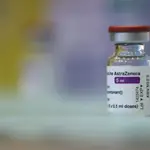

Pandemia

Muere un bebé de 7 meses por coronavirus en Portugal

El pequeño estaba ingresado en un hospital de la región de Lisboa y Valle del Tajo, actualmente la zona más afectada por la pandemia

Un bebé de siete meses ha fallecido en un hospital de la región de Lisboa a consecuencia de la covid-19, según recoge el boletín epidemiológico emitido por la Dirección General de Salud de Portugal.

El pequeño estaba ingresado en un hospital de la región de Lisboa conocida como Valle del Tajo. Esta zona acumula más de la mitad de los casos de coronavirus detectados a nivel nacional en un solo día.

Tal y como informa el diario portugués Correio da Manha, el pequeño “sufría múltiples complicaciones congénitas”.

Al menos 13.954 personas han perdido la vida en Portugal víctimas de la Covid-19, mientras que 6.158 pacientes se encuentran ingresados en hospitales, 891 de ellos en UCI.

Dado el aumento del número de los contagios, Portugal decretó un confinamiento domiciliario duro que ha incluido el cierre de escuelas y de todos los establecimientos, exceptuando los servicios esenciales.